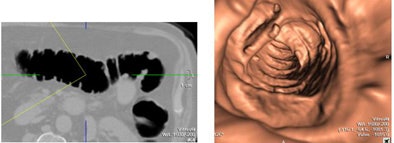

![]() |

| Results showed that most changes in renal function and electrolyte balances were mild and self-resolving after the procedure. However, two cases required pharmacologic intervention. |

"There were 10 new cases (12.8%) of electrolyte disturbances within the bowel prep period, including four cases of hyponatremia, one case of hypernatremia, four cases of hyperkalemia, and one case of hypokalemia," McLaughlin said. Most were mild and clinically insignificant, but two cases of hyperkalemia required pharmacologic intervention. Still, no patients required dialysis during the procedure, McLaughlin said.